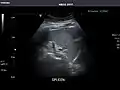

Spleen -

Spleen: Normal in size.